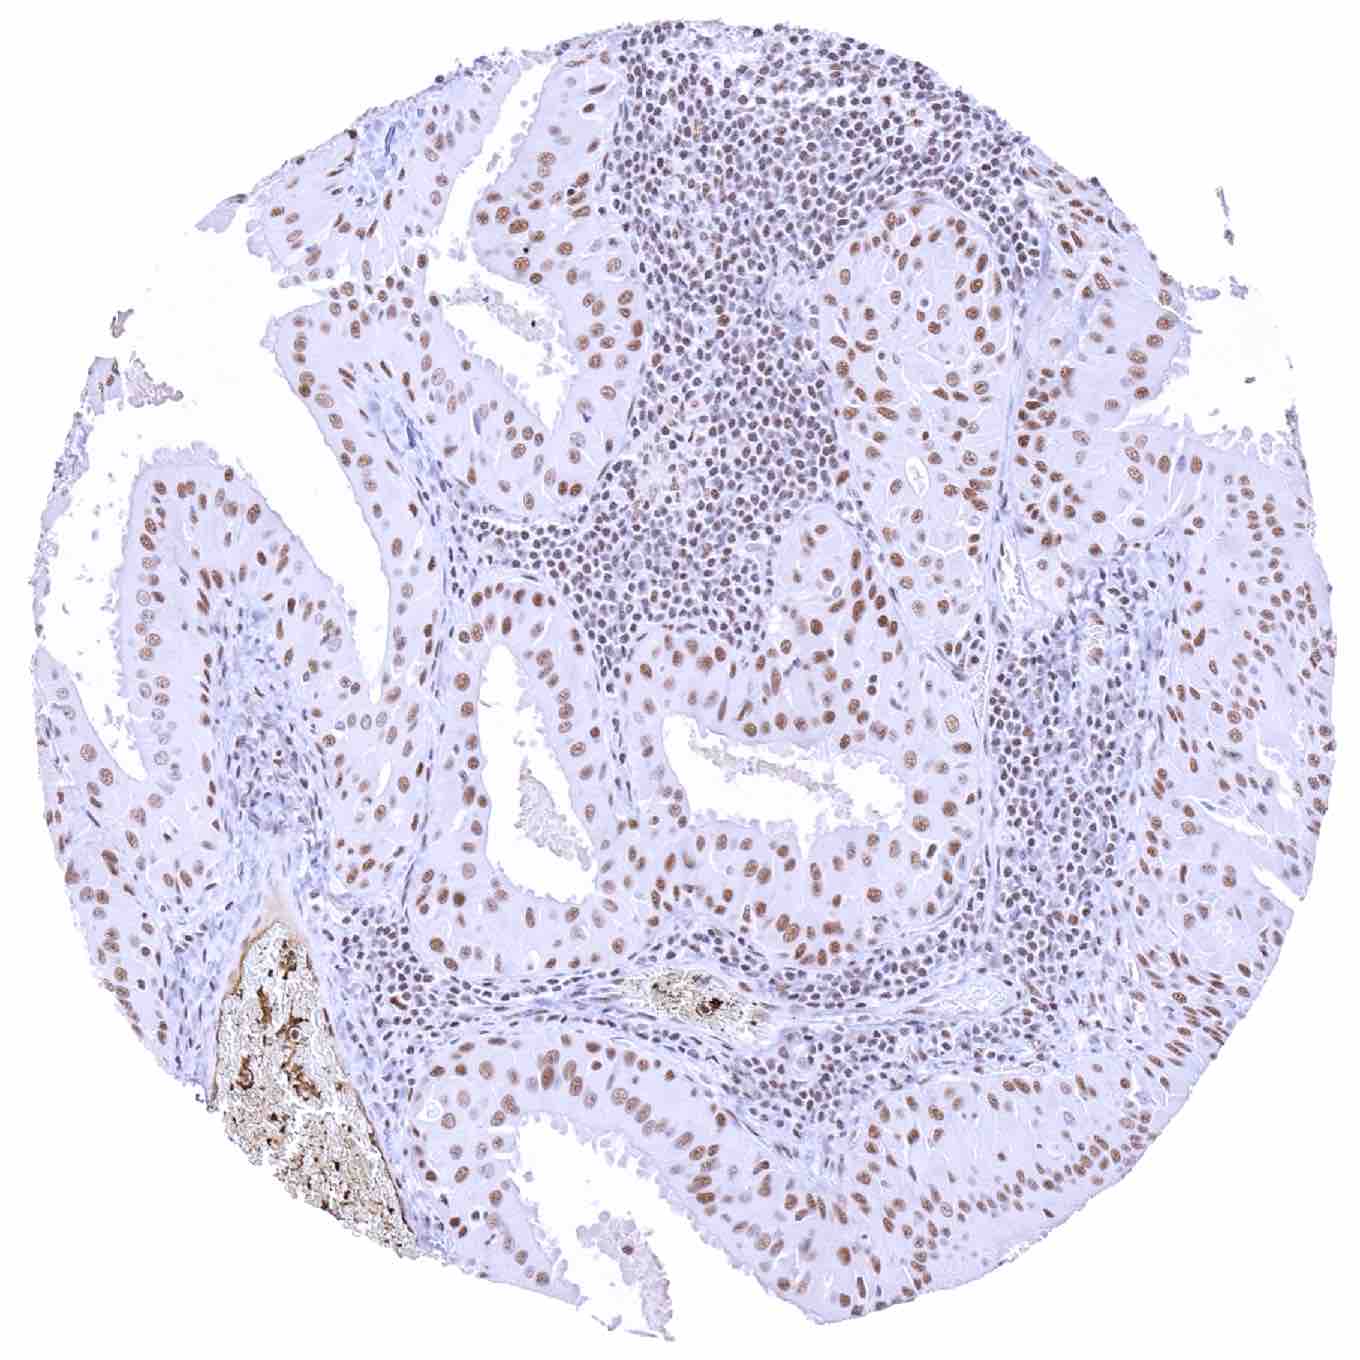

Penis – Squamous cell carcinoma with strong KDM6A staining of tumor cells